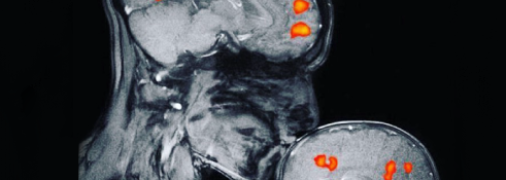

Редакция UAUA.INFO — автор портала Телеграф Сейчас на сайте 19 363 статьи автора Школа Як прості вправи з м'ячиком допомагають розвитку уваги та дісципліни в школярів: лайфхак для вчителів Звездные родители Джоан Роулинг: Неужели вам больше не о чем поговорить, кроме как о моем весе Психология Почему родителям сложно принять, что их ребенок неидеальный Здоровье и уход Правда ли, что средиземноморская диета полезна для беременных Психология Почему родители не верят в подростковую депрессию: рассказывает психолог Отношения Вся правда о МРТ-снимке матери и ребенка, который гуляет по сети Успешная мама Когда идёшь рожать, приготовься оставить за дверью свое достоинство Звездные родители Кейт Миддлтон беременна в четвертый раз: принцесса Шарлотта проговорилась в школе Школа Школьника дразнили за самодельную футболку и вот, что сделали взрослые Психология Игровая зависимость у детей: почему без смартфона ребенку скучно Показать больше